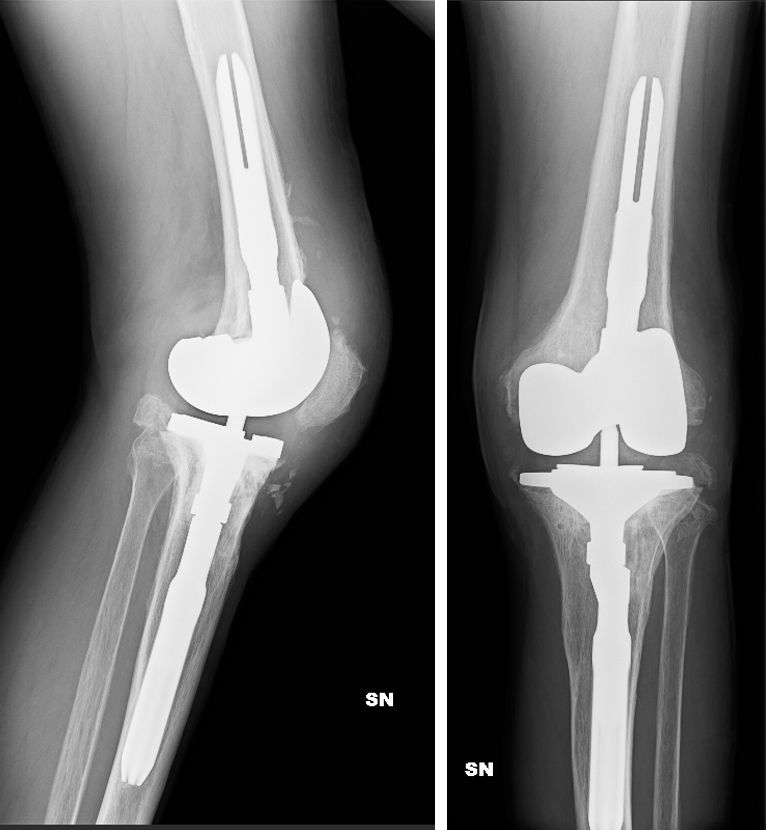

During implantation all the different options for stem length and offset, spacers, blocks and sizes can be preselected and every feature of the implant is already known and can be assembled. In many cases the preop plan fits very well with the final intraoperative solution (fig. 10-12).

The 3D model accurately reproduces all the bony landmarks that will be used for surgery and can be cut and manipulated with the surgical instruments. The model can then be sterilised, marked and taken into the operating room to help orient the surgeon and placing the components. The advantage of 3D printed models is demonstrated by bone loss after infection with Case 1 (Figs. 13 and 14) and after aseptic loosing with Case 2 (Figs 15 and 16).

Once the model is assembled, the surgeon can go to the operating room with peace of mind, knowing that only minimal modifications will be required. Nevertheless, this type of preoperative planning allows for a significant reduction in the instruments and materials used during surgery. The lack of capsular and ligament components is a limitation of this technique and therefore a way to implement this in the model needs to be investigated, for example by using varus-valgus stress radiographs to reproduce the same amount of laxity in the model (Fig. 21).

The economic aspect must also be taken into account. The 3D model costs about 500 euros, which can be reduced by intensive use, but saves time and other costs. Once the reproducibility of the system is proven (Fig. 22), it will be possible to eliminate all unnecessary materials and instruments from the operating theatre, thus saving costs for storage, sterilisation, transport and operating time.